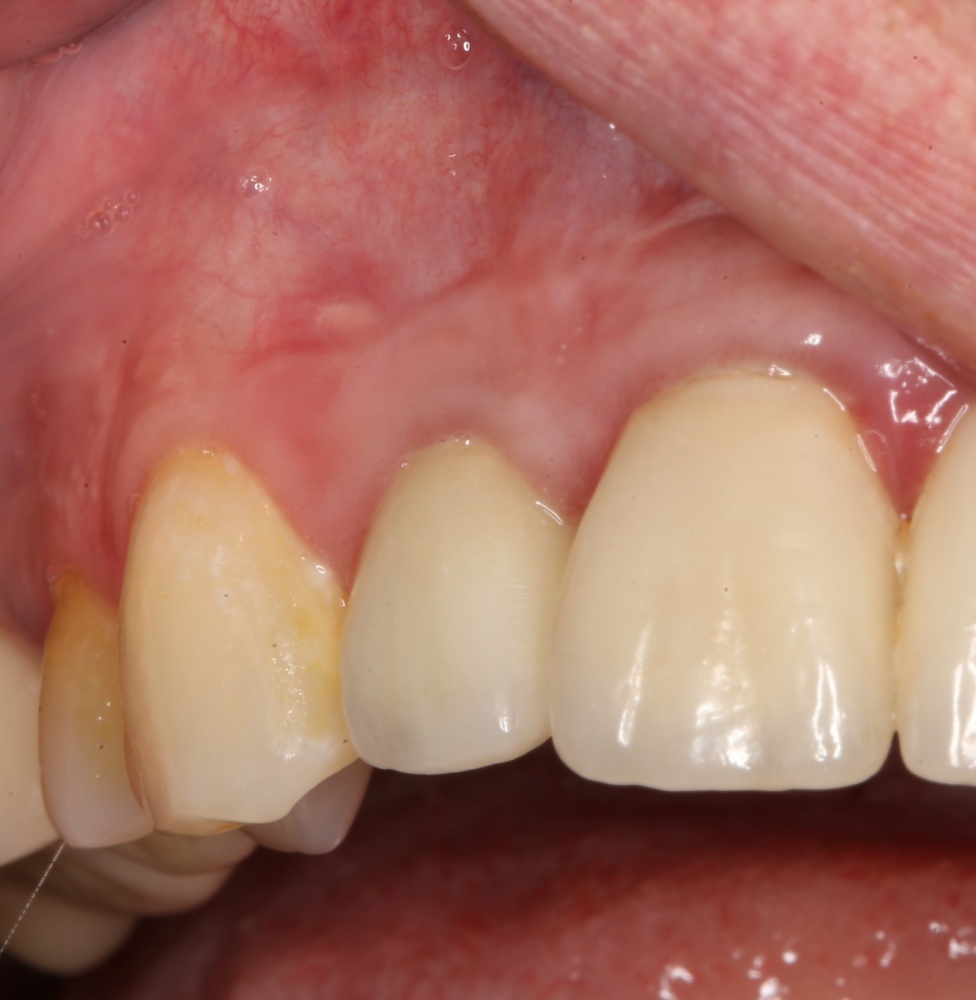

Редко, очень редко, обычно при немедленной имплантации, мы можем обойтись без искусственной десны:

Такие клинические ситуации мы относим к категории «ПОВЕЗЛО!», потому как чаще всего для создания зубов нужной формы и высоты, протезу необходим какое-то основание, компенсирующее убыль кости.